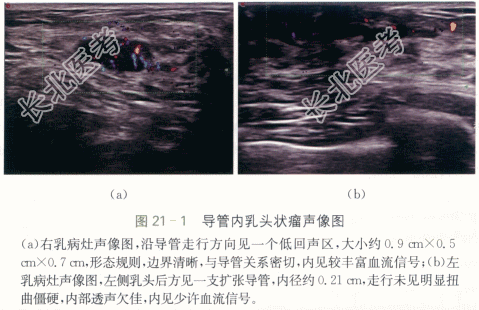

双乳导管内乳头状瘤,伴局部导管上皮增生。